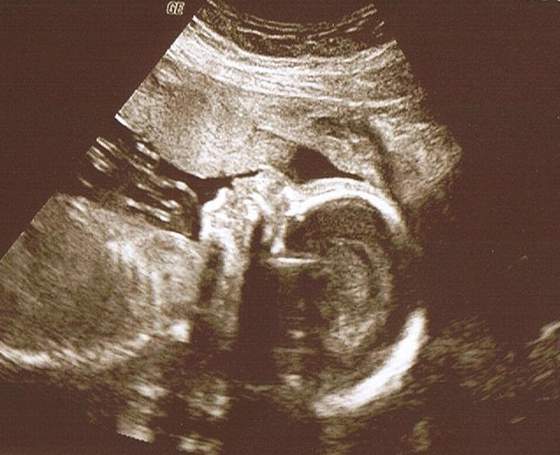

anka26,07 ,Szczebiotka, NomiMalone uwierzcie mi, macie piękne dzieciaczki! poprostu cudownie sie to ogląda

Zobacz załącznik 506927 18+2 wg OM